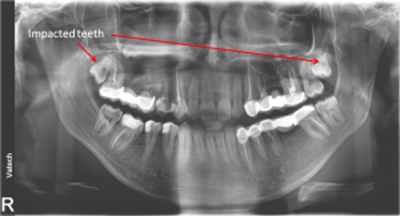

• Poor tooth and root positions

• Impacted teeth

impacted teeth